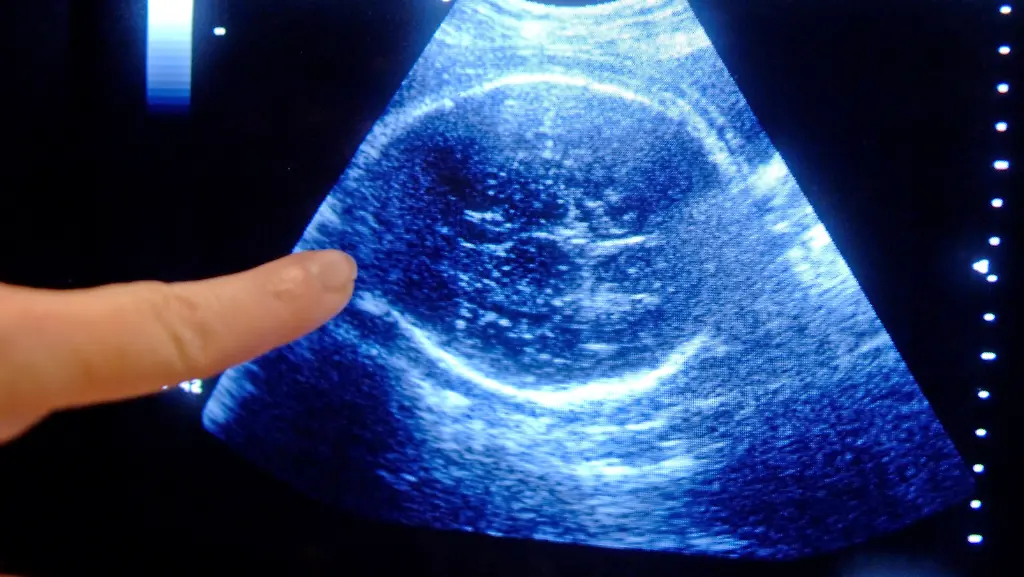

Drei Ultraschall-Untersuchungen gehören zum Standard - eines pro Trimester. Viele Frauen lassen aber fünf und mehr vornehmen.

(Foto: picture alliance / dpa)

Zu viel Ultraschall, zu viele Untersuchungen: Fast alle Schwangeren nehmen Vorsorgemaßnahmen in Anspruch, die in den Richtlinien gar nicht vorgesehen sind. Hierzu zählen etwa mehr als drei Ultraschalluntersuchungen und spezielle Blut- oder Herztonmessungen. Dies zeigt eine aktuelle Studie der Bertelsmann-Stiftung, für die knapp 1300 Mütter kurz nach der Geburt befragt wurden.

Bei der Befragung gab fast die Hälfte der Frauen mit normaler Schwangerschaft an, mehr als fünf Ultraschalluntersuchungen gemacht zu haben. Die Mutterschaftsrichtlinien sehen aber nur drei vor. Auch scheint eine spezielle Herzton- und Wehenmessung (CTG/Kardiotokographie) längst zur Routine zu gehören. Obwohl diese Untersuchungsmethode nur bei drohenden Frühgeburten und anderen Auffälligkeiten vorgesehen ist, ließen 98 Prozent die Untersuchung durchführen - im Schnitt sogar öfter als vier Mal.